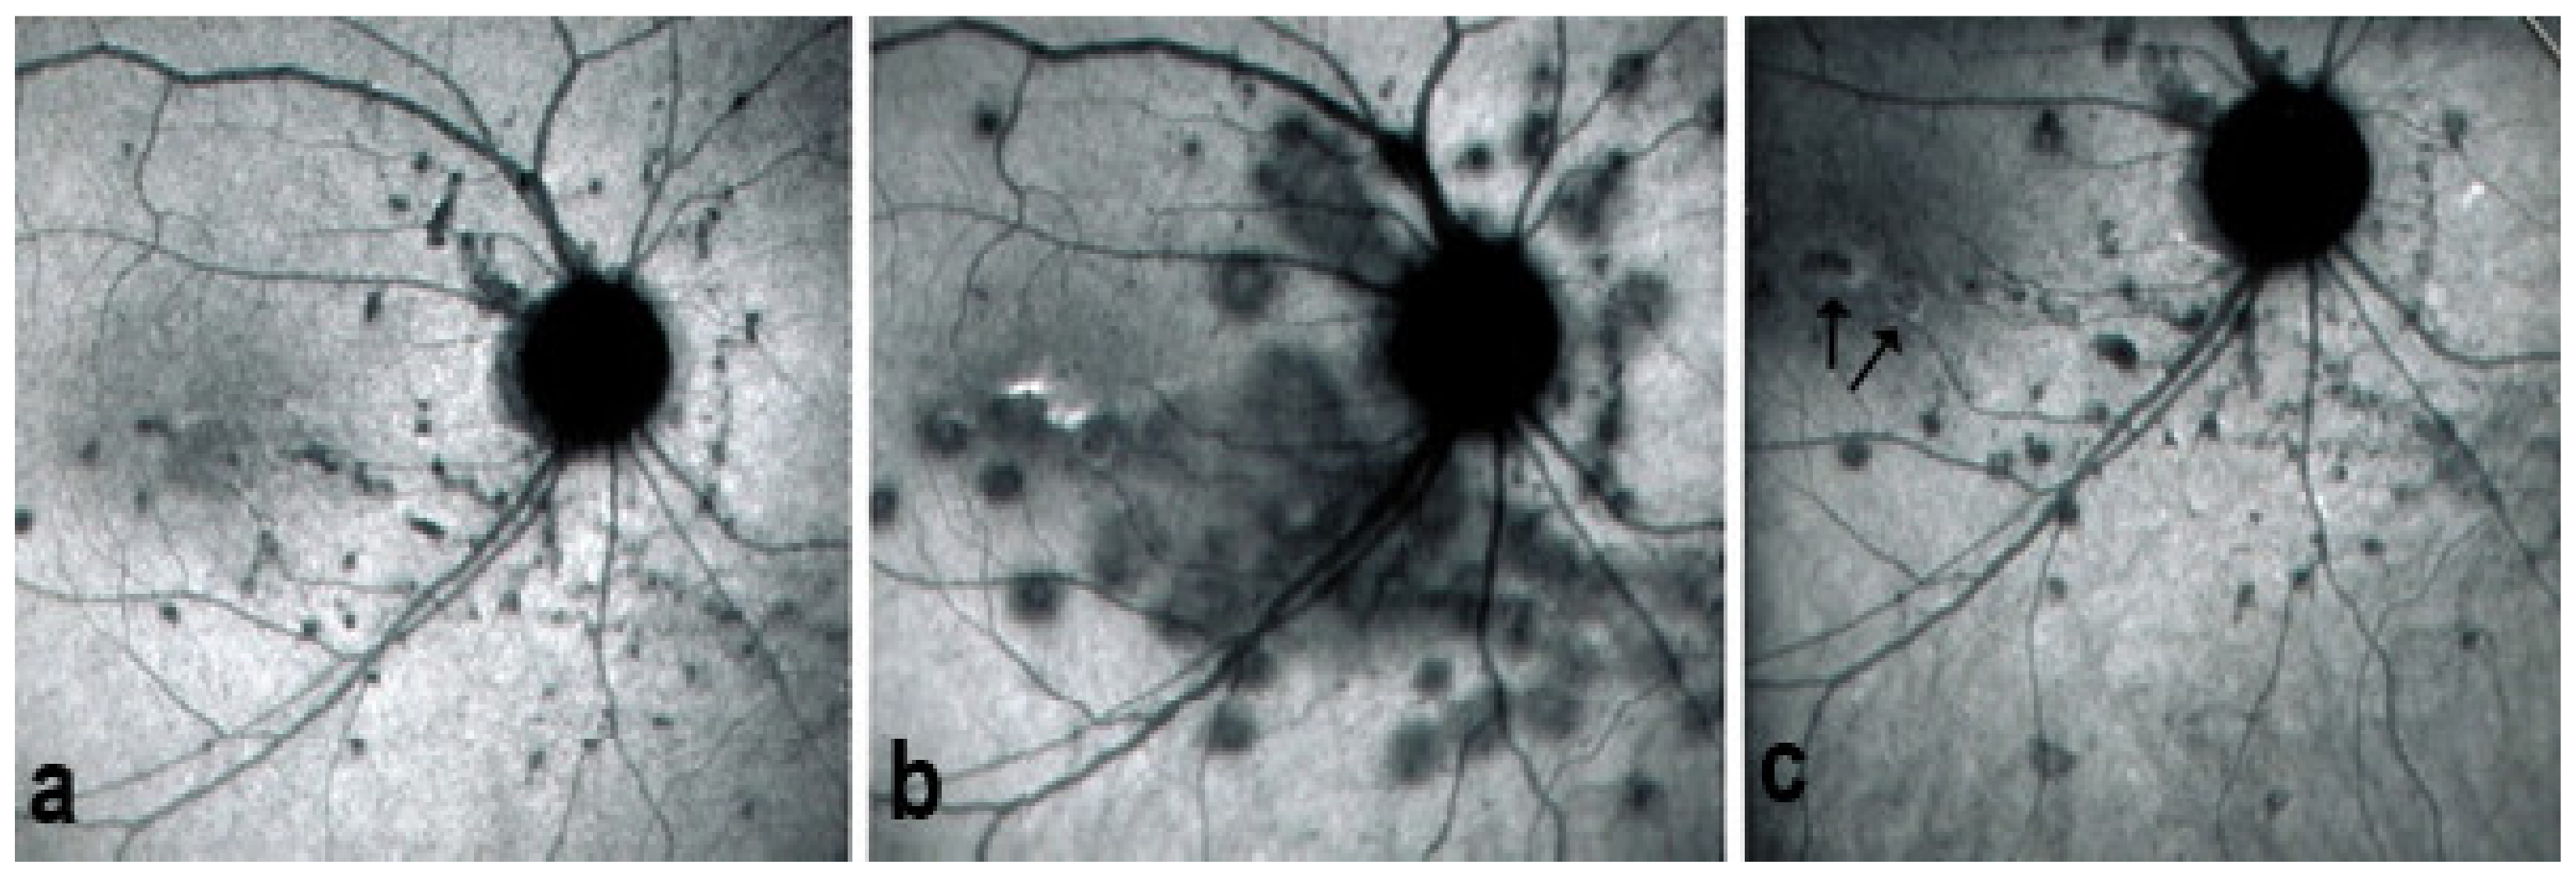

Figure 14.

MFC. ICGA time sequence. (a): shows quiet stage. Middle picture (b) shows reactivation of MFC eight months later. (c): shows healed stage of choriocapillaritis six months later after systemic corticosteroid therapy.

Figure 19.

FA pictures of MFC at presentation (a), after 1 month (b) and 4 months (c). Patchy hyperfluorescent areas are seen at presentation around optic disc and along temporal superior arcade, indicating staining of retina caused by ischaemia of outer retina (a), still present at 1 month (b), almost resolved after 4 months (c).

Figure 20.

ICGA pictures of MFC at presentation (a), after 1 month (b) and 4 months (c). Peripapillary confluent hypofluorescence and scattered hypofluorescent areas along superior temporal arcade at presentation (a), which almost completely resolved after one month (b). However, at 4 months, (c) hypofluorescent areas are still seen.

Figure 21.

BAF pictures of MFC at presentation (a), after 1 month (b), and 4 months (c). On the right column of pictures (left eye), hyperautofluorescent areas corresponding to the FA and ICGA lesions can be seen at presentation (a) which, on the (b), have slightly progressed at one month with return to almost normal autofluorescence after 4 months (c). BAF delineates lesions even with more precision than ICGA.